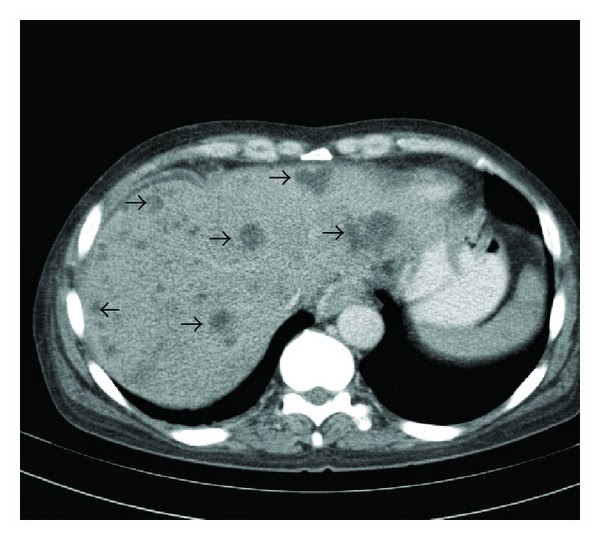

Абсцесс печени кт

Абсцесс печени кт 109 фото